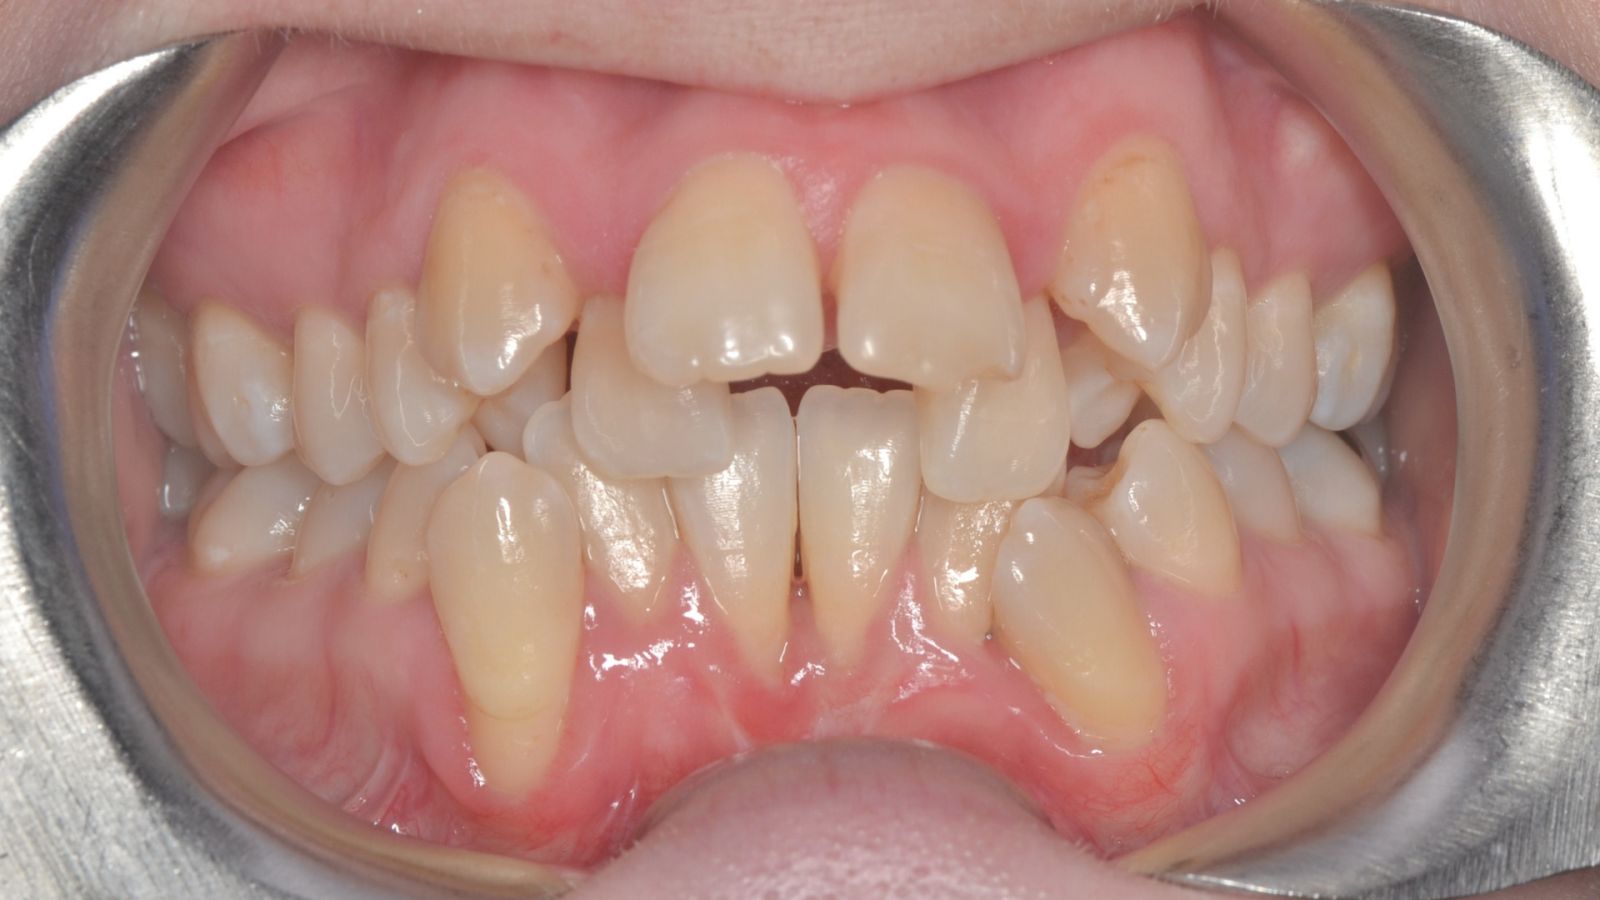

Tratamiento de ortodoncia invisible y reconstrucción estética. Logramos recuperar la armonía de su sonrisa y corregir el apiñamiento dental mediante un tratamiento discreto y cómodo, que le permitió continuar con su vida diaria con total confianza.